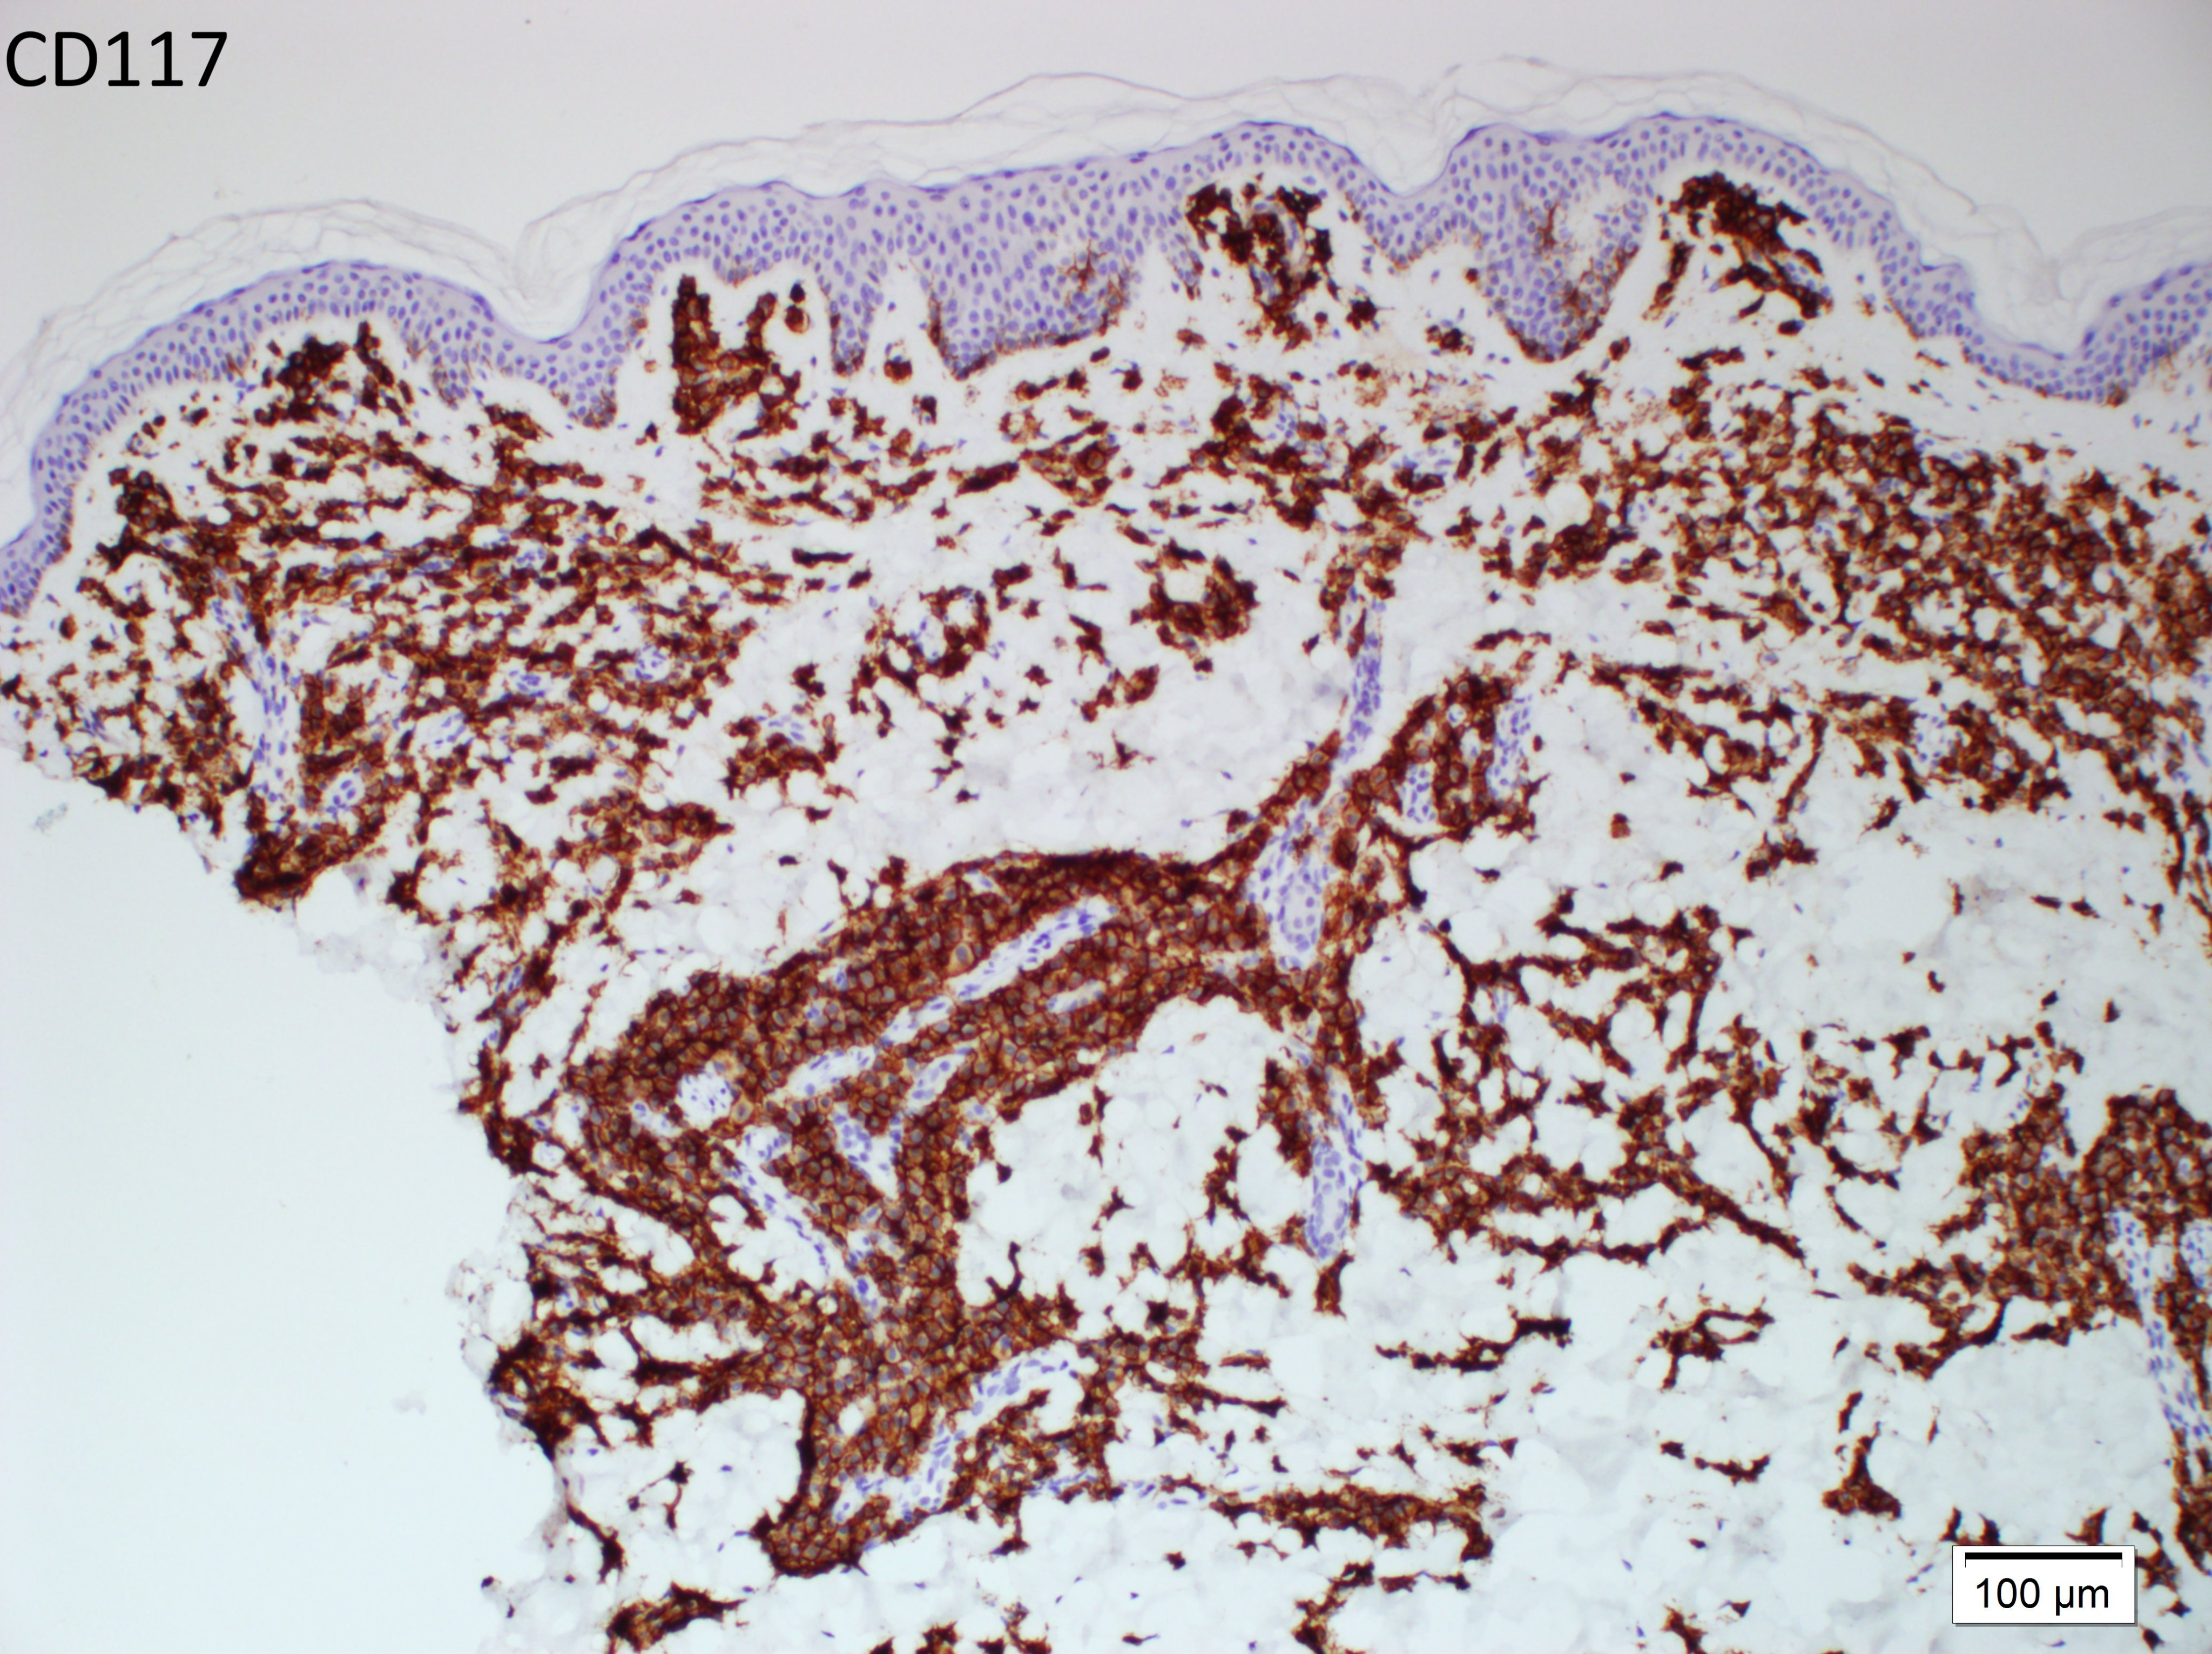

Vulvar skin biopsy. Erythematous pruritic eruption. Your diagnosis?